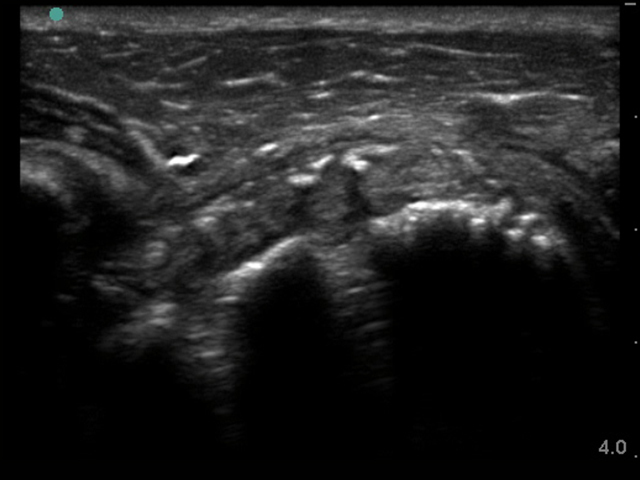

Imagen de hombro postoperación supratransversal con suturas